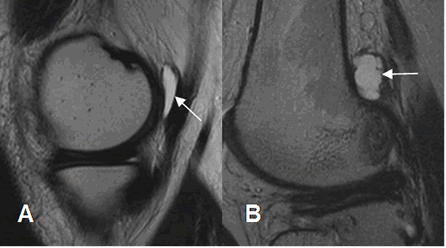

Fig 186. Bursitis.

A y B: RM sagital en T2. Bursitis del músculo semimembranoso en A y del gemelo externo en B.